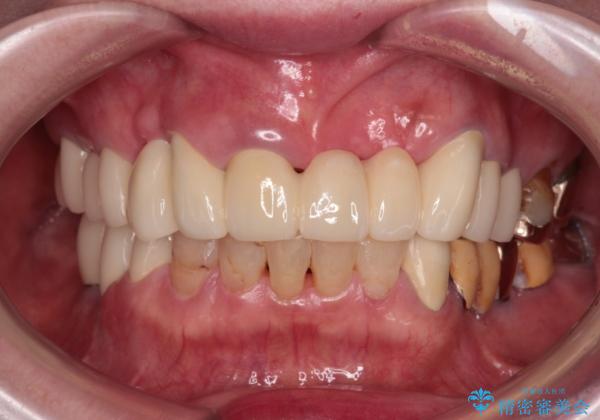

前歯をきれいにしたい インプラントや部分矯正を用いた総合歯科治療

- 抜歯の必要な前歯や、以前治療した前歯のクラウンの外観を気にして来院された患者様です。

上顎犬歯や下顎大臼歯は、必要なところはインプラントを埋入することとしました。

クラウンが不適合であったり、根管治療の必要なほどの痛みのある歯であったり、見た目の気になる前歯などをオールセラミッククラウンに補綴治療を行うこととしました。